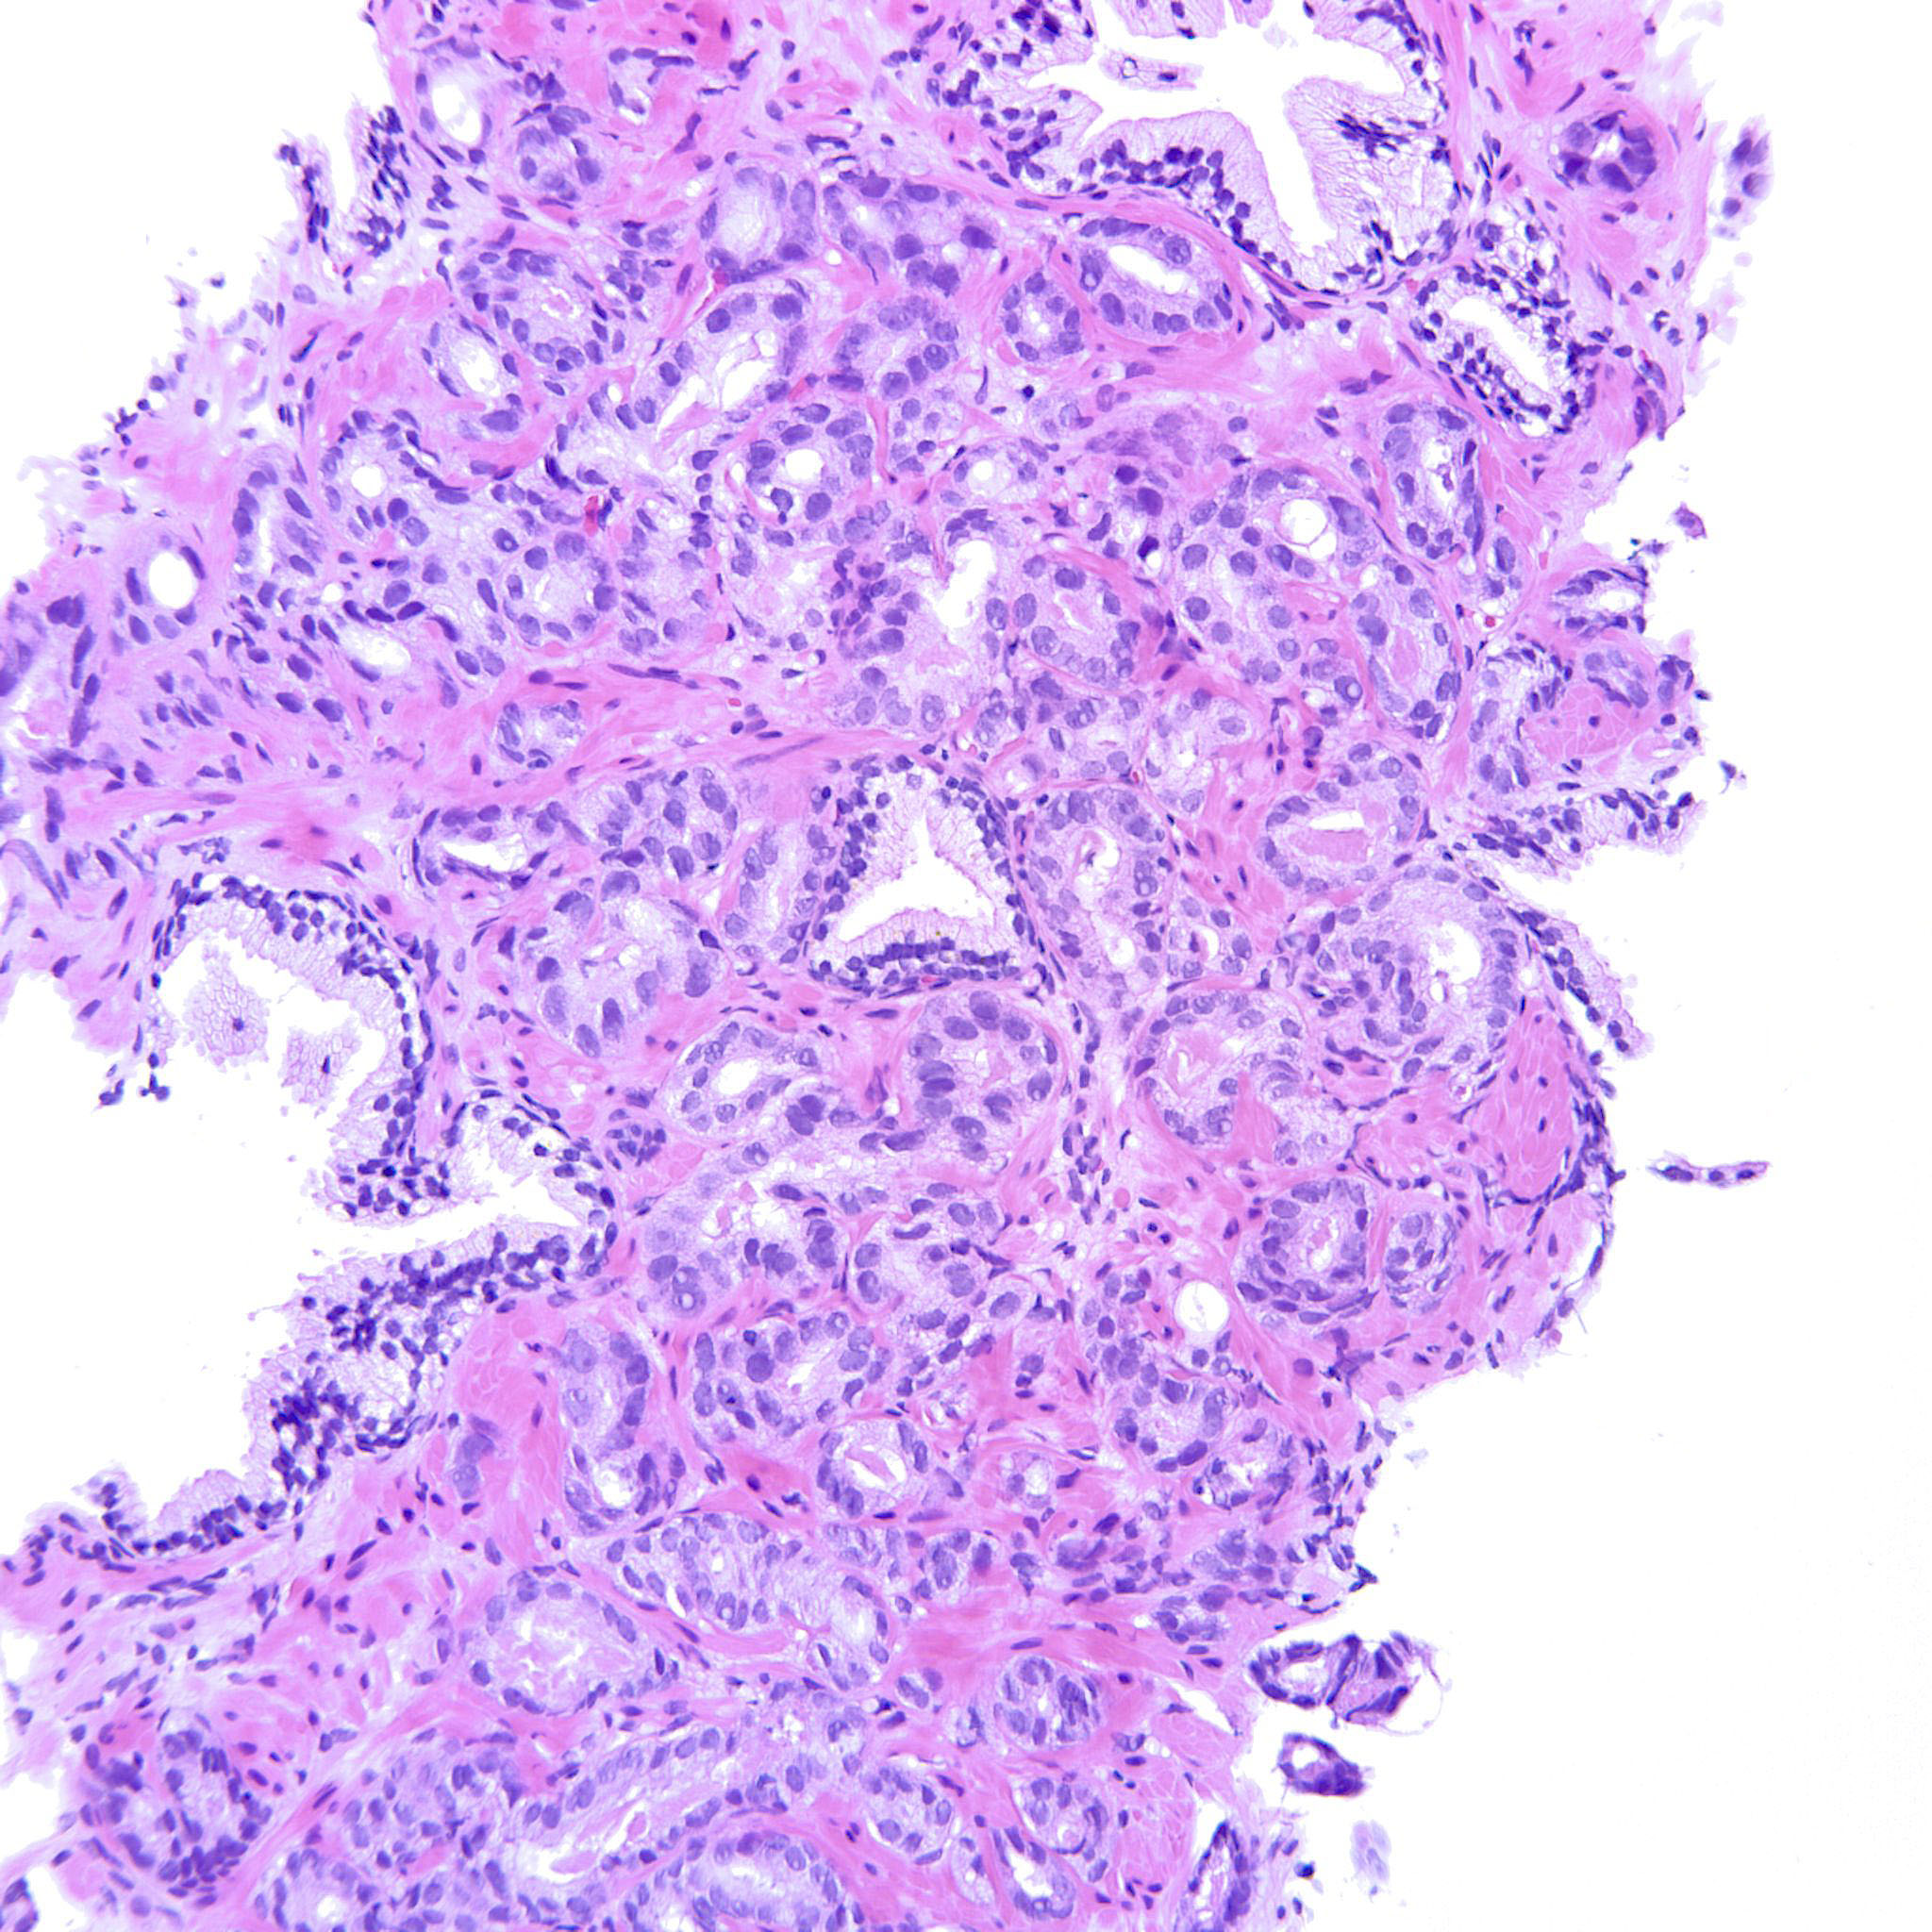

Prostate cancer grading

Case ID: 207